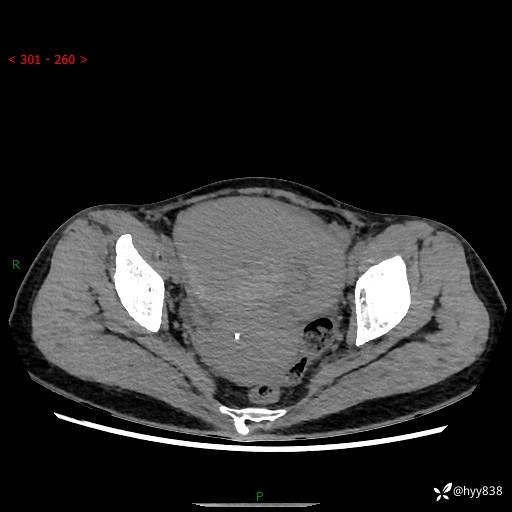

【患者信息】:女,50岁

【主诉】:外院超声发现腹盆肿块,为进一步诊治来我院,门诊已“盆腔肿块”收入院。

腹盆CT平扫+增强

【临床诊断】:盆腔肿瘤